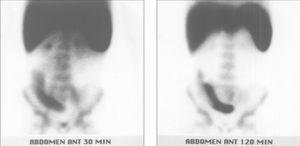

En las GLM realizadas durante el seguimiento de la enfermedad en los pacientes ya tratados (fig. 2) la concordancia de resultados con la valoración clínica en cuanto a la presencia de síntomas se produjo en 22 de 29 casos (tabla 2). En 5 pacientes asintomáticos la GLM fue patológica aunque con un grado de inflamación leve. Al igual que en los estudios diagnósticos, el índice clínico ha aumentado significativamente con la gravedad gammagráfica (p < 0,005) (fig. 3), con una aceptable correlación con el índice de actividad gammagráfica (r = 0,62; p < 0,001).

Figura 2.Niña de 10 años con importantes síntomas de enfermedad inflamatoria intestinal y estudio analítico gravemente alterado. Colonoscopia y biopsia compatibles con enfermedad de Crohn. Ecografía normal. La gammagrafía con leucocitos marcados en el momento del diagnóstico (izquierda) muestra inflamación pancolónica de carácter moderado, con mayor afectación en ciego y colon ascendente. Tras el tratamiento (derecha) se normaliza la gammagrafía con leucocitos marcados lo cual es indicativo de buena respuesta con ausencia de actividad inflamatoria.